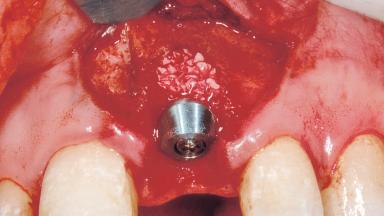

Immediate Placement of an Implant in a Maxillary Left Central Incisor Site

Bone Augmentation Horizontal|Simultaneous

Augmentation Materials Xenogenous|Membrane

Placement Protocol Immediate implant placement

Socket Integrity Damage to one or more bone walls

Bone Volume Damage to one or more socket walls